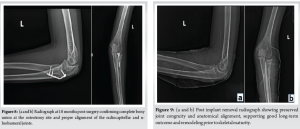

The patient was reviewed 1 year 6 months after surgery and presented with full, painless range of motion of the left elbow compared to the opposite side (Fig. 7). Radiographs taken showing union of radial head at the time of follow up (Fig. 8). The patient also underwent implant removal before skeletal maturity to allow the natural course of remodelling and preventing limb length discrepancy (Fig. 9).